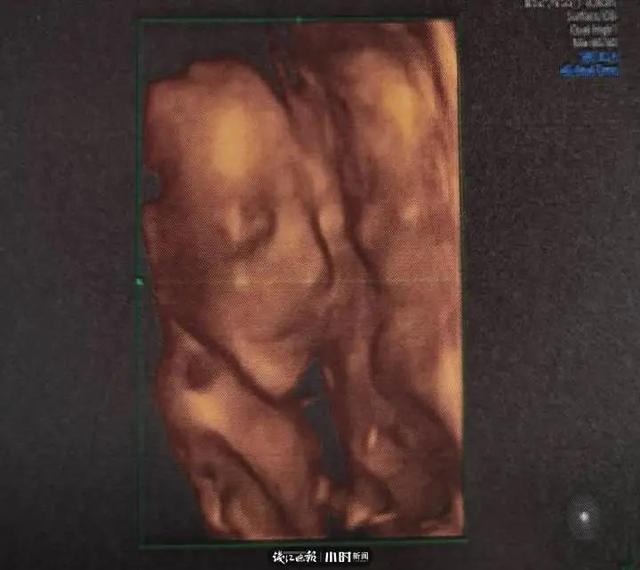

前两天,韩颖去做了四维彩超。这瞄准爸妈第一次与宝宝晤面,看到了小宝宝模糊的五官后,小两口很激动。

韩颖这次又发了一条朋侪 圈向老公梁笑天喊话:“韩先生 来兑现允许了……”

韩颖说,小宝宝手长脚长像爸爸的。